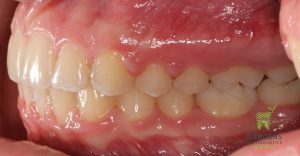

Class II malocclusion treatment correcting crowding and occlusion (bite changes)